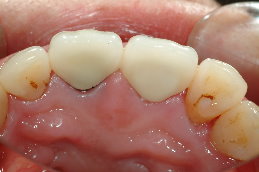

患者蔡小姐10年前,因為蛀牙,因而製作右上正門牙及左上正門牙共2 顆,但由於長期金屬黑邊露出、陶瓷龜裂,相當不美觀,並且右上正門牙的牙齦腫脹病患經介紹至本診所,尋求顯微根管治療及審美牙科治療,希望能徹底解決此問題。

二、左上正中門齒,牙齦腫脹,使用馬來亞膠針,發現左上正中門齒根管病變(圖二)。